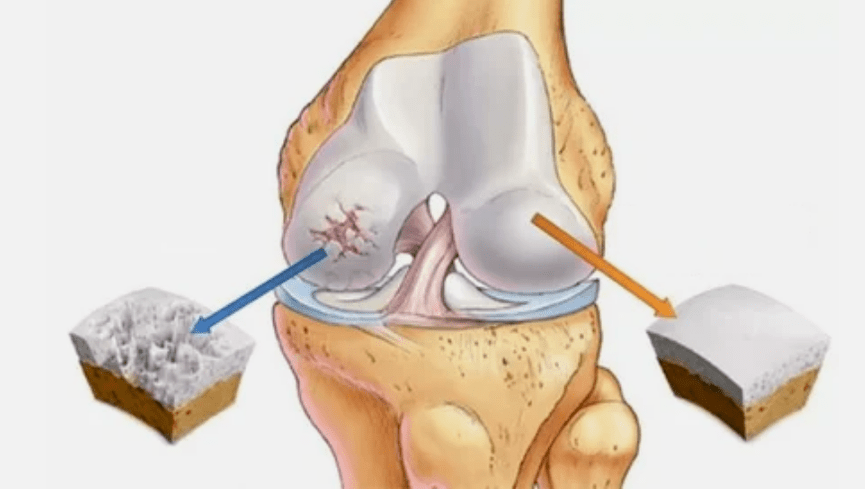

- Pathologies de revêtement Hyalin. La minceur du cartilage conduit au remplacement de ses tissus pathologiques: les structures osseuses.

- Des croissances anormales apparaissent dans le cartilage - ostéophytes.

- La violation de l'anatomie naturelle du cartilage et des os provoque la surcharge de zones de cartilage saines. La destruction des tissus conjoints sans traitement progresse constamment et conduit à l'invalidité.

Lorsque le degré de maladie augmente, les processus pathologiques sont encore aggravés. En fin de compte, l'ensemble du cartilage Hyalin est détruit.